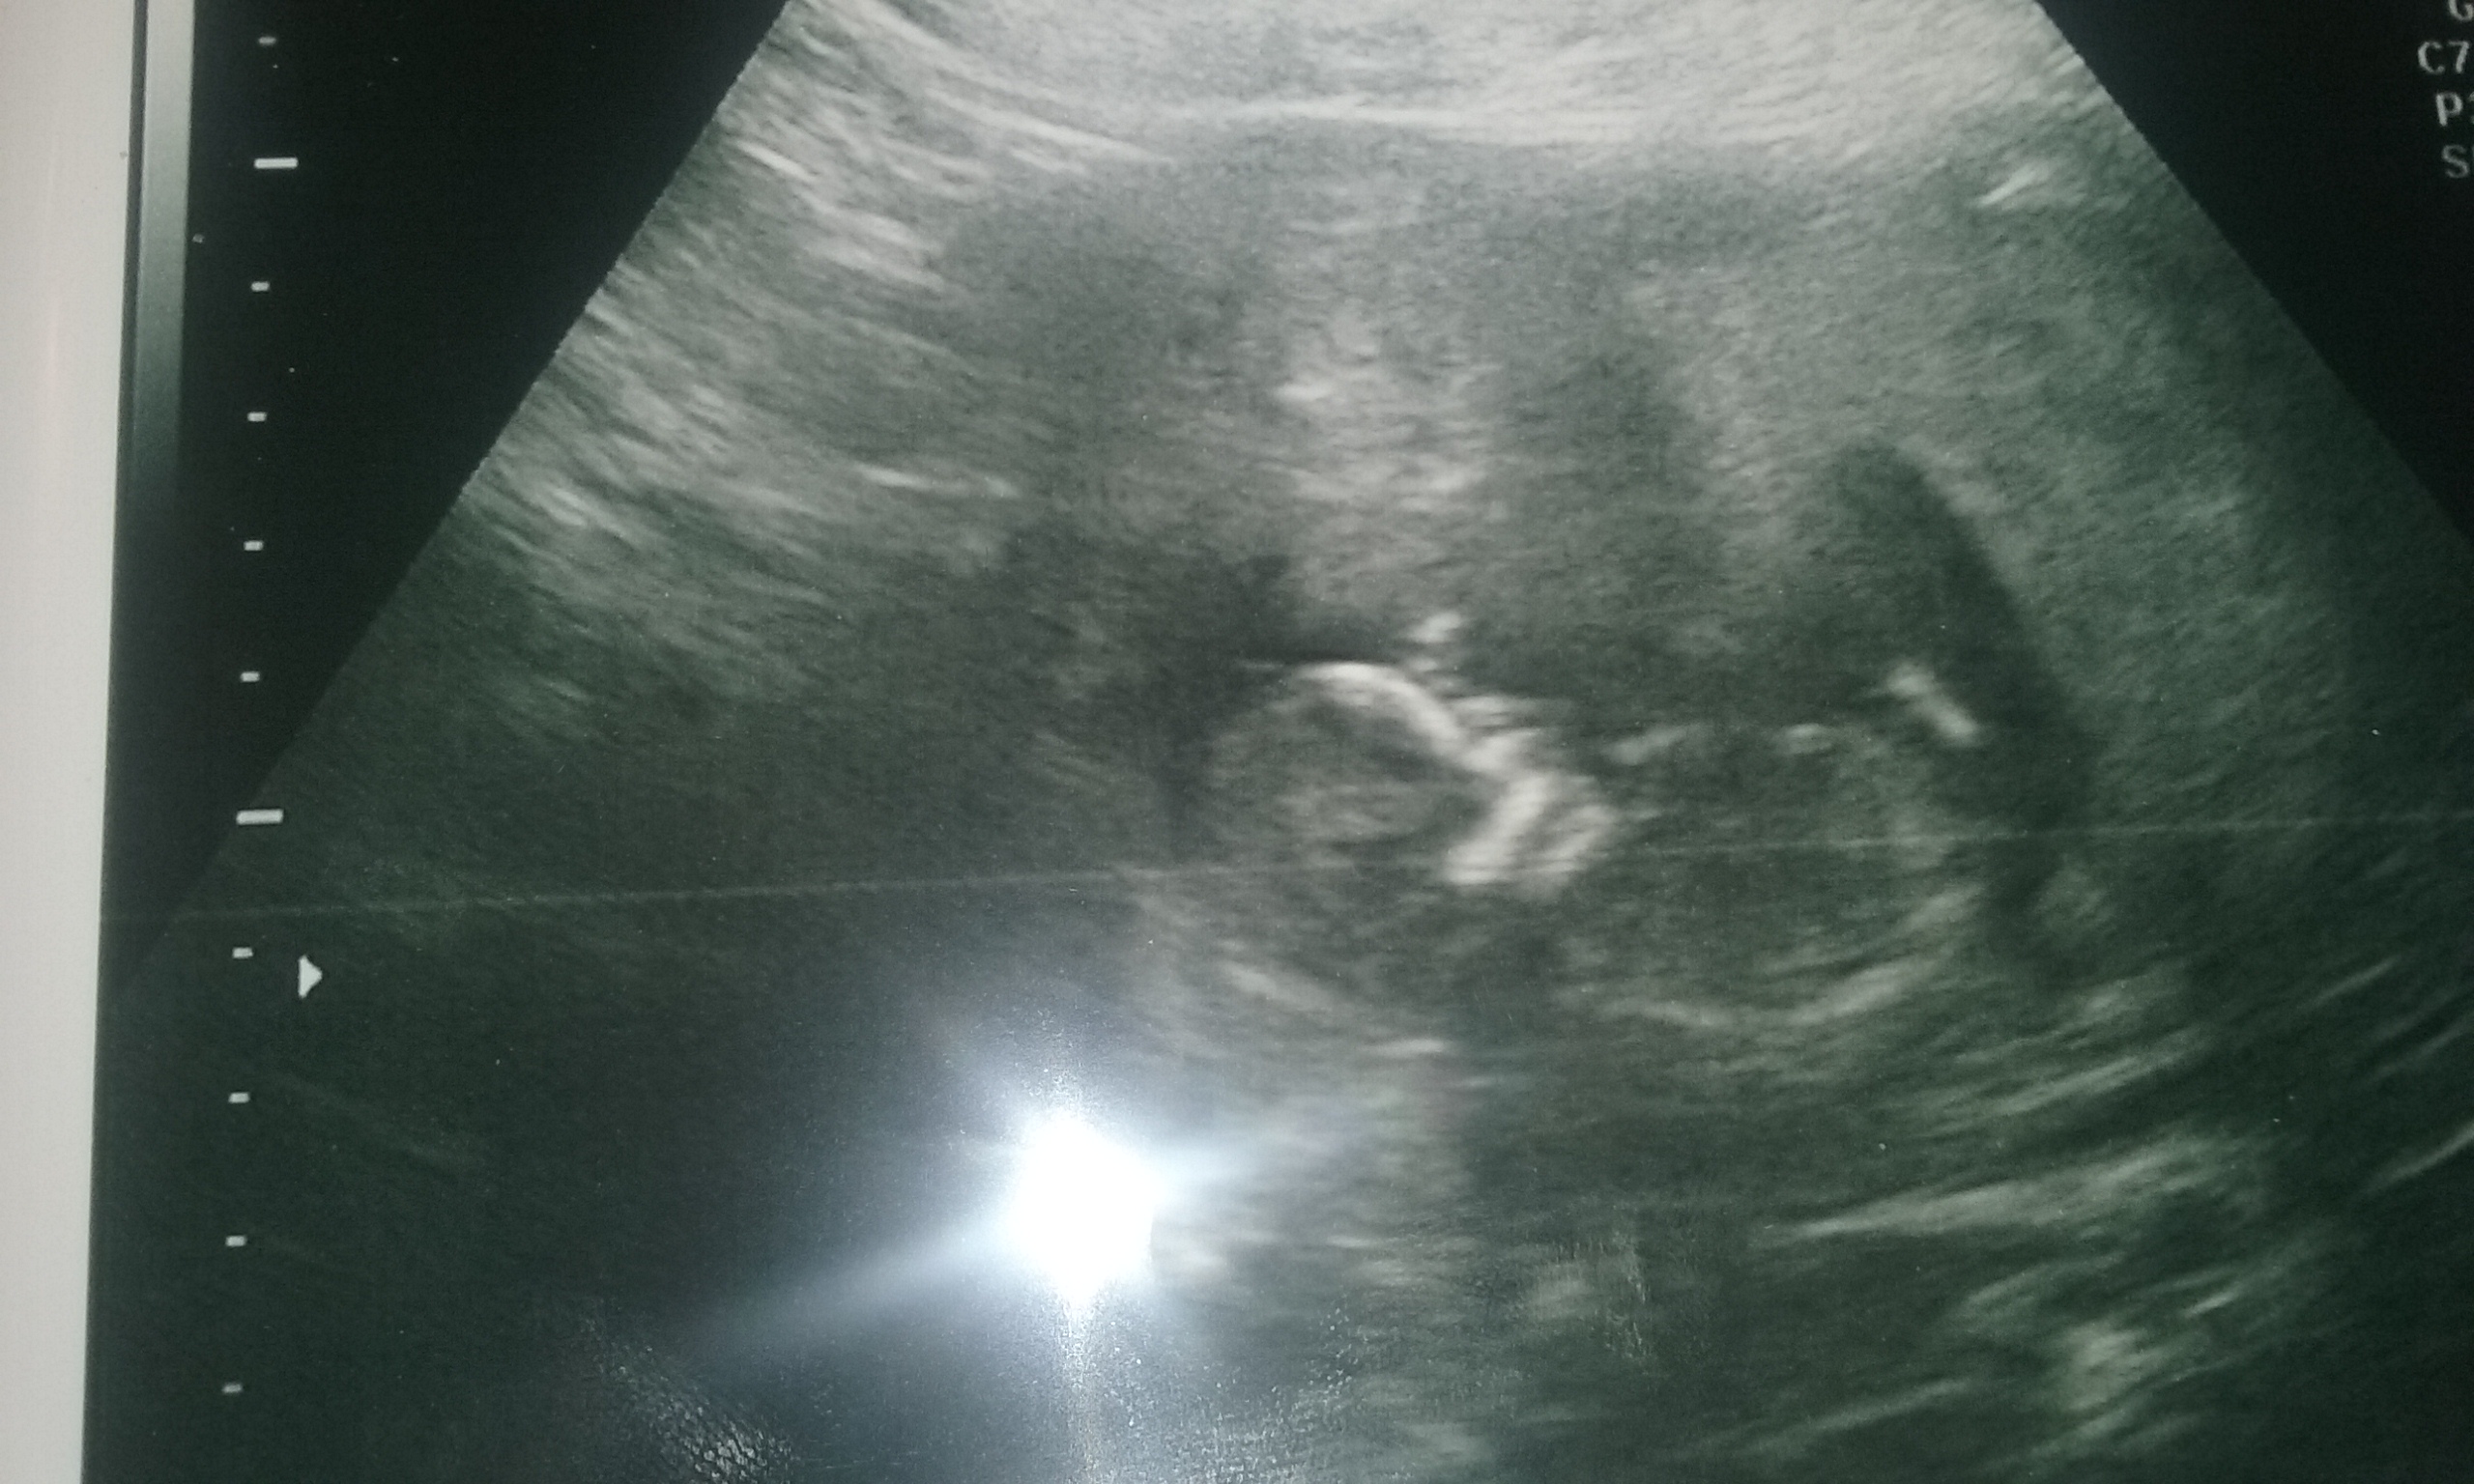

Attachment 10891

This is a pic showing the girlie two white lines poking again out of the bottom of baby, the lower part of the spine detail is missing so can make it look like an angled boy nub, so again its all about the detail.

So you can see above how on an ultrasound a girls bright white nub line is flat and how it can often appear as longer as her inner part is pointing out of the bottom of baby and how it can look like two lines.